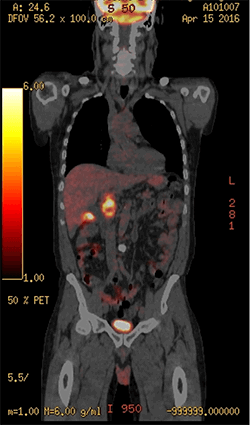

The patient had a past medical history of type 1B choledochal cyst and cholelithiasis causing biliary colic and multiple common bile duct (CBD) stone extractions. He presented to a community hospital with abdominal pain typical for biliary colic and five pound weight loss. The patient’s total bilirubin was 1.2, with an elevated alkaline phosphatase (ALP) at 200. A CT scan was performed demonstrating portal lymphadenopathy and a possible gallbladder mass (Figure 1).

Figure 1: CT Figure showing large portal nodes (arrow to enlarged node)